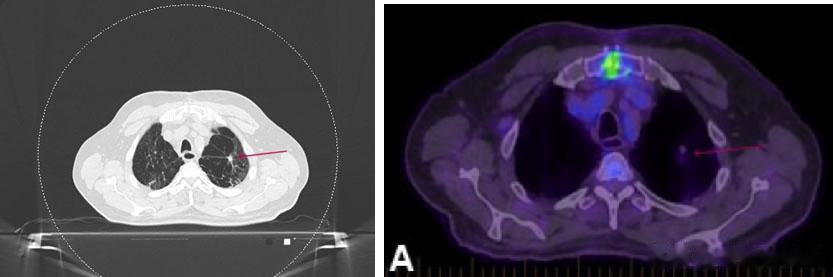

但就在放疗前的CT模拟定位中,医生意外发现他的肿瘤竟然明显变小了,直径从原先的17mm缩小到了9mm。复查PET/CT也显示肿瘤的代谢活性明显降低,SUV值从9.7下降到1.5。

计划放疗前的模拟CT和PET/CT影像